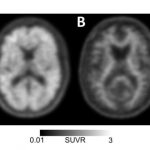

A first-of-its-kind national study has found that a form of brain imaging that detects Alzheimer's-related "plaques" significantly influenced clinical management of patients with...